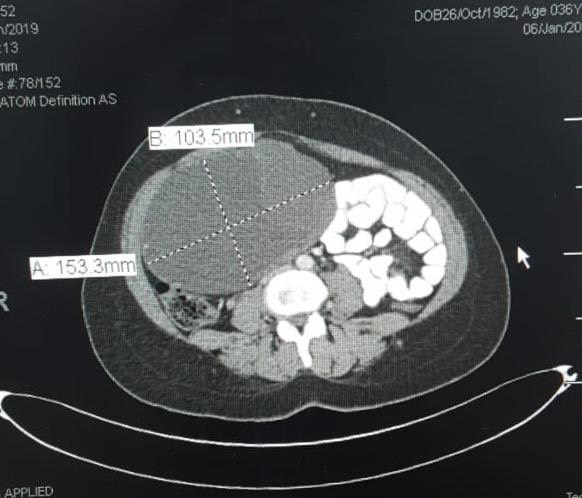

An adnexal mass (mass of the ovary, fallopian tube, or surrounding connective tissues) is a common gynecologic problem. In the United States, it is estimated that there is a 5 to 10% lifetime risk for women undergoing surgery for a suspected ovarian neoplasm. Adnexal masses may be found in females of all ages, from fetuses to older adults, and there are a wide variety of types of masses.  Today, the surgical treatment has become more conservative and less invasive; hence, a laparoscopic approach in the presence of benign cysts has become a golden standard. In the past, patients with previous abdominal surgery were discouraged from undergoing laparoscopic surgery because of its increased risk of bowel injury caused by needle and trocar insertion. Complications occur two times more frequently in patients with previous laparotomy in a study of long series. The potential risk for injury of organs adherent to the abdominal wall during veress needle or trocar insertion as well as the necessity for adhesiolysis and its attendant complications are the two major specific problems constraining surgeons from performing laparoscopic cystectomy/ oophorectomy for patients with previous abdominal surgery. Herein, we report a case of a 32-year-old woman P4 + 2 with history of previous four cesarean section and a following laparotomy for interval sterilization presented to our clinic with abdominal mass, discovered by ultrasound scan, managed by a laparoscopic approach.